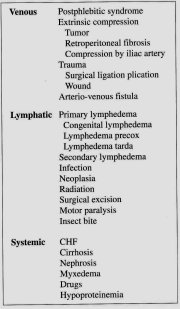

| 07:58, 15 בנובמבר 2012 | טבלאוריד515.png (קובץ) |  |

333 קילו־בייטים | Motyk | 1 | |